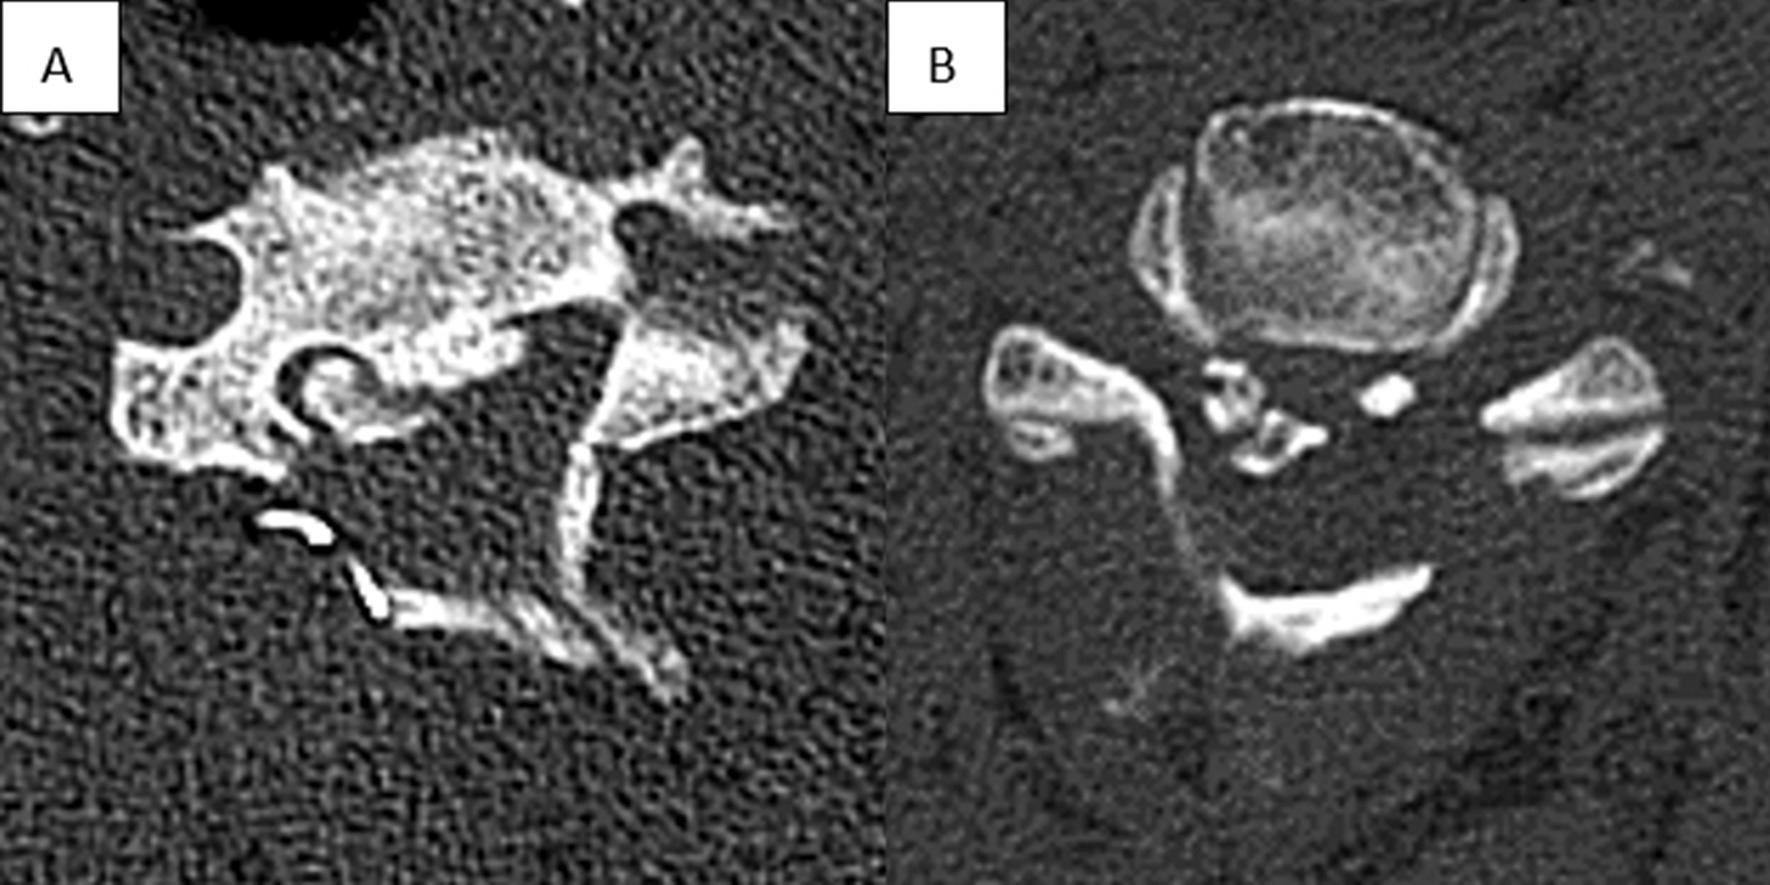

The factors affecting neurological outcomes with unilateral open-door laminoplasty have been controversial. The purpose of this study was to evaluate the impact of the characteristics of ectopic bone on poor neurological outcomes after unilateral open-door laminoplasty.

We retrospectively analyzed the clinical data of 112 patients who underwent unilateral open-door laminoplasty from September 2017 to September 2020. According to the Japanese Orthopedic Association score recovery rate after surgery (Japanese Orthopedic Association recovery rate ≥ 50% and < 50%, respectively), all patients were divided into "poor" and "good" groups. The characteristics of ectopic bone and the position relationship between the open side and ectopic bone (for lateral ossification) in the two groups were compared and analyzed. Univariate and multivariate analyses were used to determine the risk factors for poor neurological outcome.

We identified patients with a mean age of 58.39 years and a mean follow-up of 25.43 months. Sixty (53.6%) patients experienced recovery of poor neurological function. On univariable analysis, significant predictors of poor neurological recovery were occupation rate of spinal canal > 60% (p = 0.000), ossification extending to C2 (p = 0.006), lateral ossification (p = 0.032) and opening side on the ipsilateral side of the ectopic bone (p = 0.011). Multivariate logistic regression analysis revealed that the occupation rate of spinal canal > 60% (P = 0.003), ossification extending to C2 (P = 0.041) and opening the door on the ipsilateral side for lateral ossification (P = 0.013) were independent risk factors for poor prognosis of neurological function.

An occupation ratio > 60% is the most important risk factor. Another one is ossification of the posterior longitudinal ligament extending to C2. Meanwhile, opening the door on the ipsilateral side is indeed a risk factor for lateral ossification. Better neurological function may be obtained by choosing the opposite side of the heterotopic bone as the open side. Therefore, the design of the surgical plan should comprehensively consider these factors.